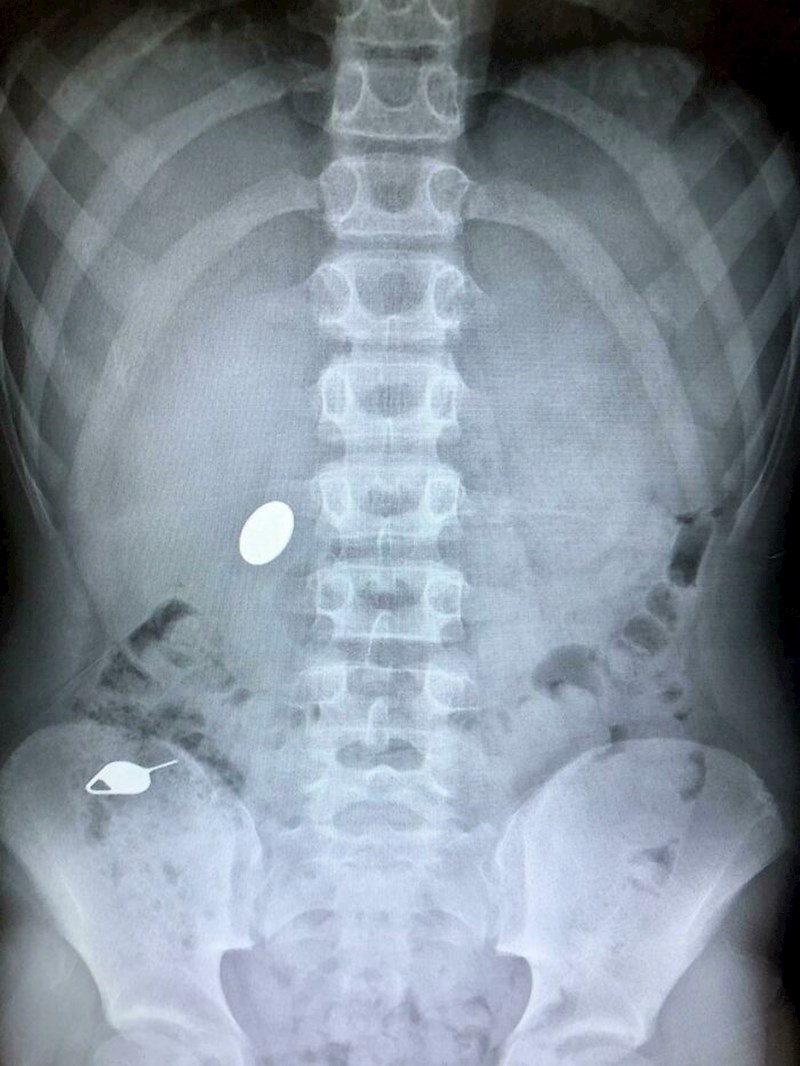

Da, ovo će se definitivno urezati u sjećanje!